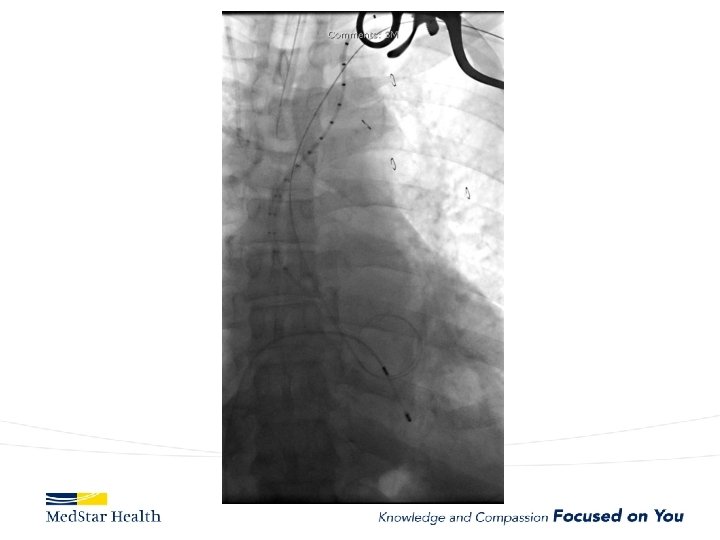

How Do We Treat • Open repair-unacceptable morbidity and mortality • TEVAR – Improved morbidity and mortality – Coverage of primary entry tear – Additional coverage?

Aneurysms • Descending – Obvious first choice assuming anatomically favorable • Ascending – IDE, Off label in high risk patient • Arch – Available in Europe, Under Trial in US • Thoraco – Available in Europe, Under Trial in US

Ascending Aorta • Currently off label unless in IDE • Challenges – Devices too long or too small for ascending – More complex terrain • Entire cardiac output • Valve/coronaries below • Inomminate above. – New Commercial Devices now available (shorter/tapered)

Current experience with ascending TEVAR JTCVS 2017 Nov 22, Roselli et al. 2006 to 2016 39 patients very high risk for open surgery – A dissection (12, 31%), – intramural hematoma (2, 5%), – pseudoaneurysm (22, 56%), – chronic dissection suture line entry tear (3, 8%). TEVAR in 36 Operative mortality 13%; 5 deaths all in Type A dissections Other complications: – stroke in 4 patients (10%), myocardial infarction in 2 patients (5%), tracheostomy in 2 patients (5%), and dialysis in 2 patients (5%).